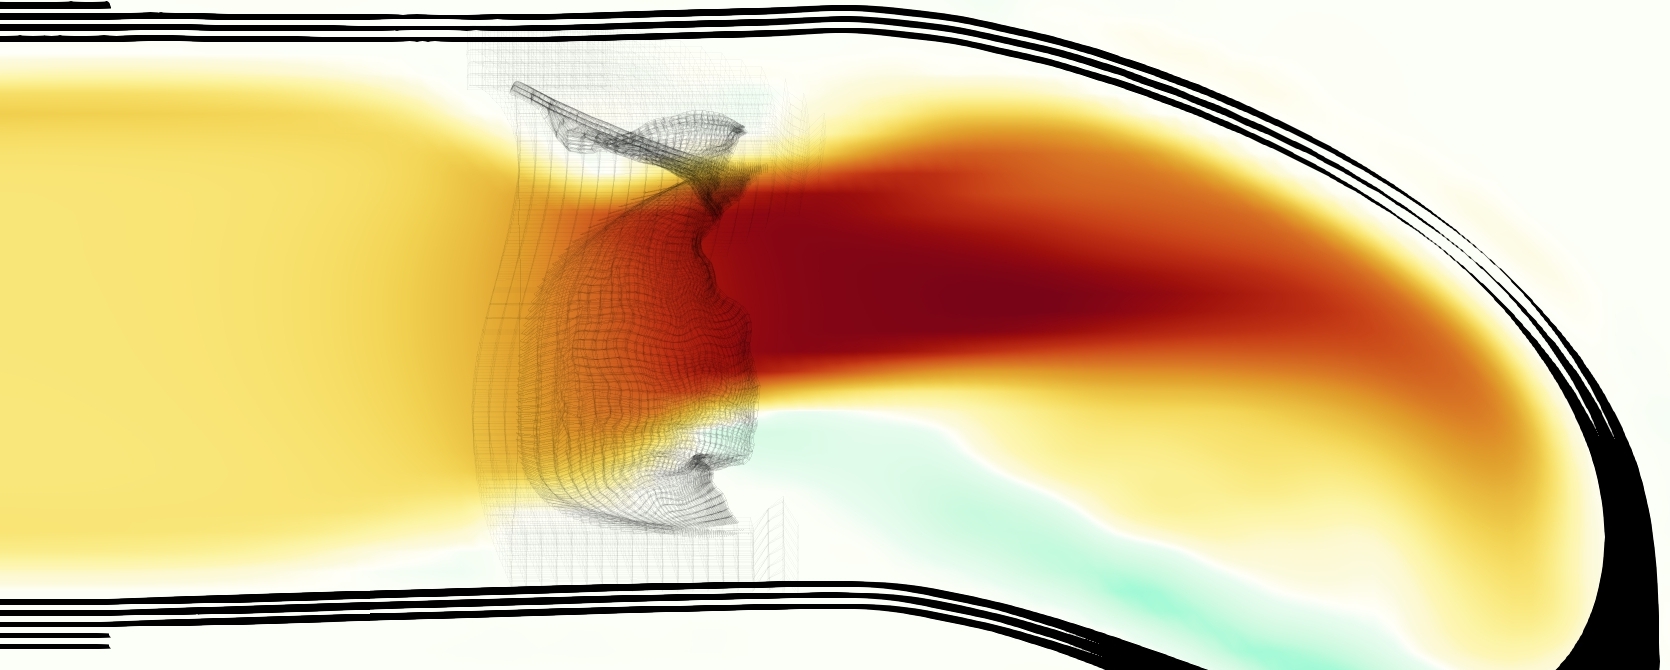

The emergent hemodynamics showed excellent qualitative agreement with experiments. Slice views of the axial component of fluid velocity ( component) in the sagittal plane that cuts through the center of the vessel, parallel to the flow direction, are shown in Figure 5. The flow in both the simulation and the experiment began to accelerate at the same time, with a jet forming through the open valve leaflets. The velocity, angle, and shape of the jet agreed well between the two cases during systole. The simulation captured the slight upward angle of the jet, which was not fully centered in the vessel. It also matched the location where the jet impacts the wall and the slower speed of the jet as it turns with the MPA downstream. As the flow decelerated, the fluid along the interior curve of the vessel reversed first while forward flow persisted where the jet was strongest, as seen in both the simulation and experimental results.

In both the experiment and the simulation, a separation region of reverse flow developed along the interior curve of the vessel under the core jet through the valve. The reverse flow began to develop at the same time in the cardiac cycle and grows throughout systole. The simulation lacked reversed flow in the entire region where reversed flow was present in the experiment, but this region developed some flow separation and had much slower flow than elsewhere in the vessel. Thus, the simulation captured that this is a distinct region from the core jet through the valve opening. There was a smaller amount of slower and slightly reversed flow along the outer curve of the vessel, close to the valve annulus and scaffold support. This region was well-matched between the experiment and the simulation.

A comparison between the phase-averaged velocity resampled onto the MRI grid, the phase-averaged velocity without resampling, the instantaneous flow field without resampling and the MRI velocity field is shown in Figure 8. The coarser resolution is visible as a “stair-stepping” or “pixelated” effect on the phase-averaged resampled velocity, whereas the edges of the jet are more smooth in the phase-averaged velocity with no resampling. Otherwise, the resampled velocity appears qualitatively similar to the phase-averaged velocity with no resampling. Fine scale features were present in the instantaneous field that were lost in the phase-averaging and resampling process. There was more variation in the local velocity of the center of the jet and local areas of high velocity at the edges of the jet that suggested vortices. Vortical structures adjacent to the jet and in the areas of reversed flow were apparent. These comparisons suggest that 4D flow MRI data may lose substantial fine-scale flow features in the flow field via phase-averaging.

Of potential future interest, the phase-averaged, resampled velocity showed substantial differences from the instantaneous velocity fields, with more variation in local fluid velocity and more fine scale vortical structures visible in the simulation (Figure 8). This points to an advantage for simulations: since 4D flow MRI data is fundamentally phase-averaged, once validated, simulations provide a richer dataset when these instantaneous fluid features are of interest.